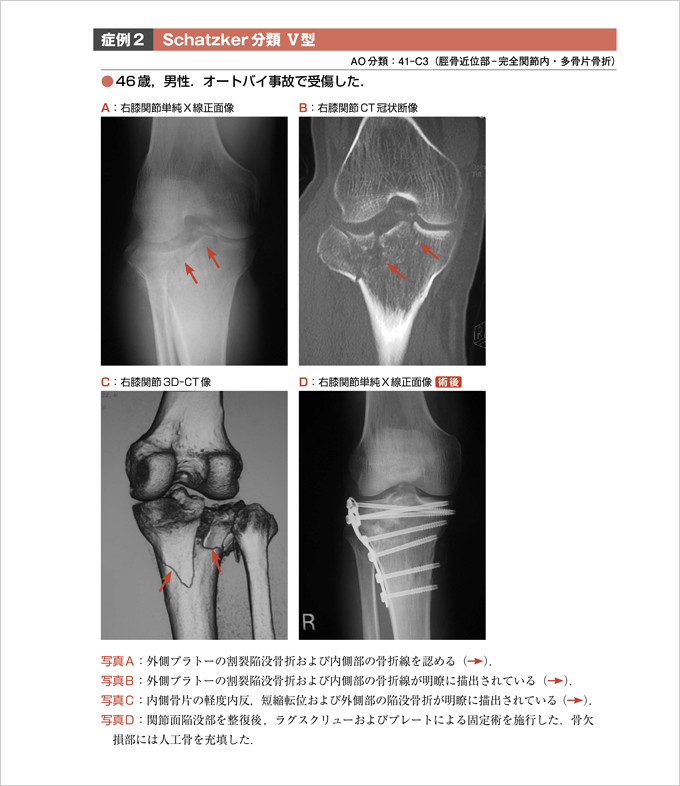

4. 脛骨プラトー骨折 [Schatzker分類]【大森俊行】

第9章『4. 脛骨プラトー骨折』より